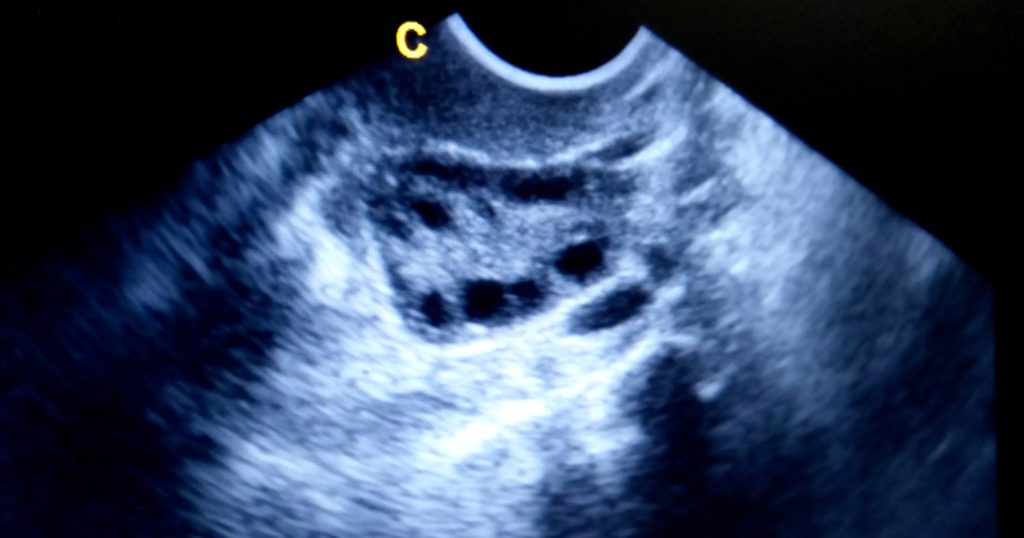

تتعدد أسباب تكيس المبايض وعوارضه، كذلك تشخيصه الذي يكون عبر الفحص السريري، أو التحاليل المخبرية أو الموجات فوق الصوتية للحوض لقياس حجم المبيضين وعلامات تكيسهما، فإليك المزيد في هذا الموضوع.

كما قلنا سابقاً، فإن التشخيص المبكر أمرٌ في غاية الأهمية لإدارة العوارض ومنع تطور مشكلة صحية طويلة، ويعد السونار أو الموجات فوق الصوتية من الوسائل التي يتم اللجوء اليها للتشخيص، ويعدّ أفضل وقت لعمل سونار تكيس المبايض، هو الفترة ما بين اليوم 12 إلى 15 من الدورة الشهرية، وتالياً، هي فترة الاباضة التي تكون بعد انتهاء الدورة الشهرية بحوالي 7 أيام.